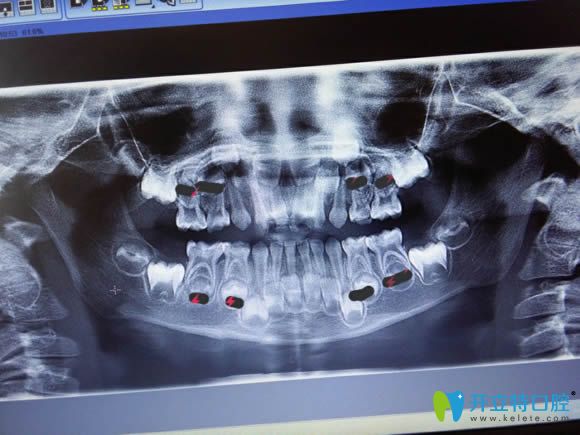

兒童牙片顯示圖

牙齒的X線片俗稱牙片,是牙醫(yī)診療的重要工具之一。通過牙片,可以了解到蛀牙的范圍,以及牙周炎癥的病變程度,還有成人年種植牙所需要的骨量、某些腫瘤等等??梢詭椭t(yī)生發(fā)現(xiàn)病變并確定其程度、范圍及治療深度,治療后也便于觀察療效。

牙片主要有全景片(大片)和根尖片(小片)兩種類型。